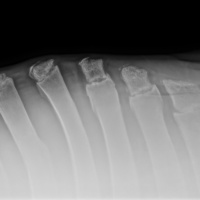

Cuattro DR HD è l'ultimo sistema radiografico digitale ad alta definizione per piccoli animali ed equini prodotto dal fornitore leader di soluzioni radiografiche digitali veterinarie.

Innovativo, veloce, efficace, sicuro e ancora più brillante: l'ultimo sistema a raggi X, Cuattro DR HD soddisfa i più alti standard nella diagnostica radiografica veterinaria.

• Visualizza i dettagli come mai fino ad ora : 17x17'’ 100 microns High definition detectors combinati con la migliore tecnologia post-elaborazione nel nostro software per immagini di altissima qualità